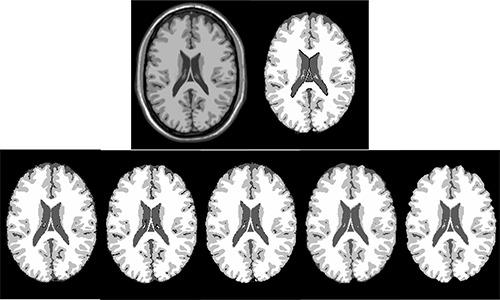

In this paper, performance evaluation of three widely used brain segmentation software packages SPM8, FSL and Brainsuite is presented. Segmentation with SPM8 has been performed in three frameworks: i) default segmentation, ii) SPM8 New-segmentation and iii) modified version using hidden Markov random field as implemented in SPM8-VBM toolbox.

The accuracy of the segmented GM, WM and CSF and the robustness of the tools against changes of image quality has been assessed using Brainweb simulated MR images and IBSR real MR images. The calculated similarity between the segmented tissues using different tools and corresponding ground truth shows variations in segmentation results.

本文对三种广泛使用的脑分割软件包SPM8、FSL和Brainsuite进行了性能评估。使用SPM8进行分割的框架有三种:i)默认分割,ii)SPM8新分割,iii)使用SPM8-VBM工具箱中实现的隐马尔可夫随机场的修改版本。

使用Brainweb模拟MR图像和IBSR真实MR图像评估了分割后的GM、WM和CSF的准确性以及工具对图像质量变化的鲁棒性。使用不同工具分割的组织与相应的真实情况之间计算出的相似度显示了分割结果的差异。